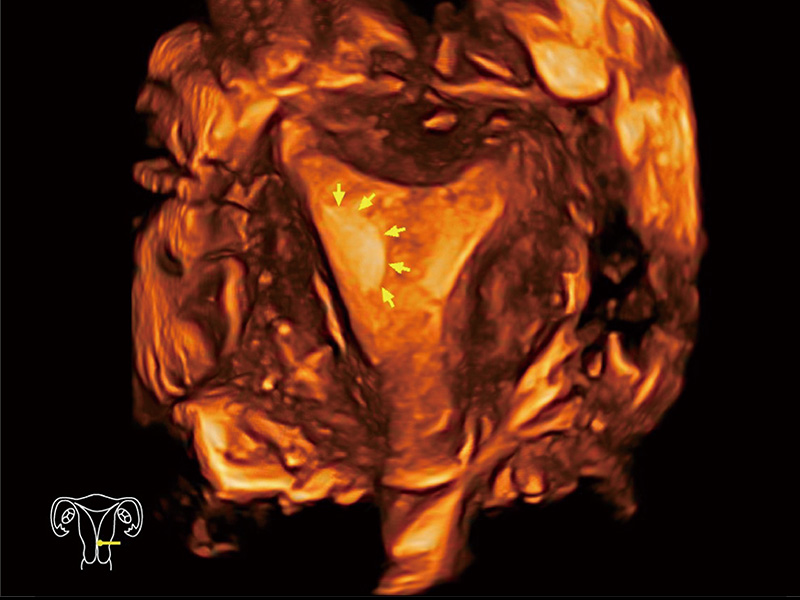

中央型宫腔粘连

腔内三维成像技术获得显著提升,超大扇角在满足日常基础扫查的同时,支持卵泡自动测量及多种三维渲染模式,为您提供更多的诊断信息,尤其是在子宫畸形的诊断,内膜及肿瘤占位观测中起到了重要的作用。